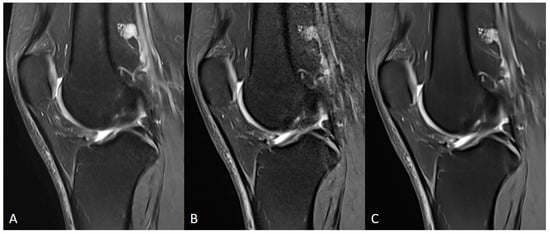

| Knee | TSES | TSE PD FS | coronal | 3:11 | 150 | 0.2 × 0.2 × 3.0 | 2 | 1 | 3 | 3790 | 44 | 150 | 100 | 14.6 |

| TSEDL | TSE PD FS | coronal | 1:33 | 150 | 0.5 × 0.5 × 3.0 | 1 | 1 | 3 | 3580 | 41 | 150 | 120 | 13.7 | |